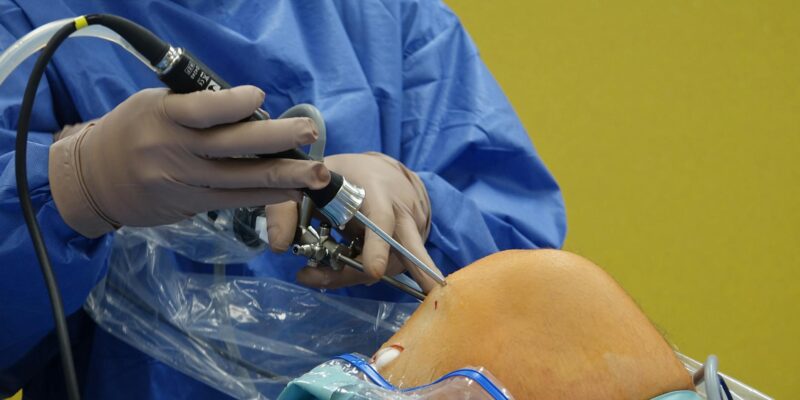

Inner Knee Pain: What It Really Is in 2026

Inner knee pain often gets dismissed as a minor ache, but its causes can be surprisingly complex and even point to more serious issues. I’ll break down why you might be feeling pain on the inside of your knee and what you can actually do about it.